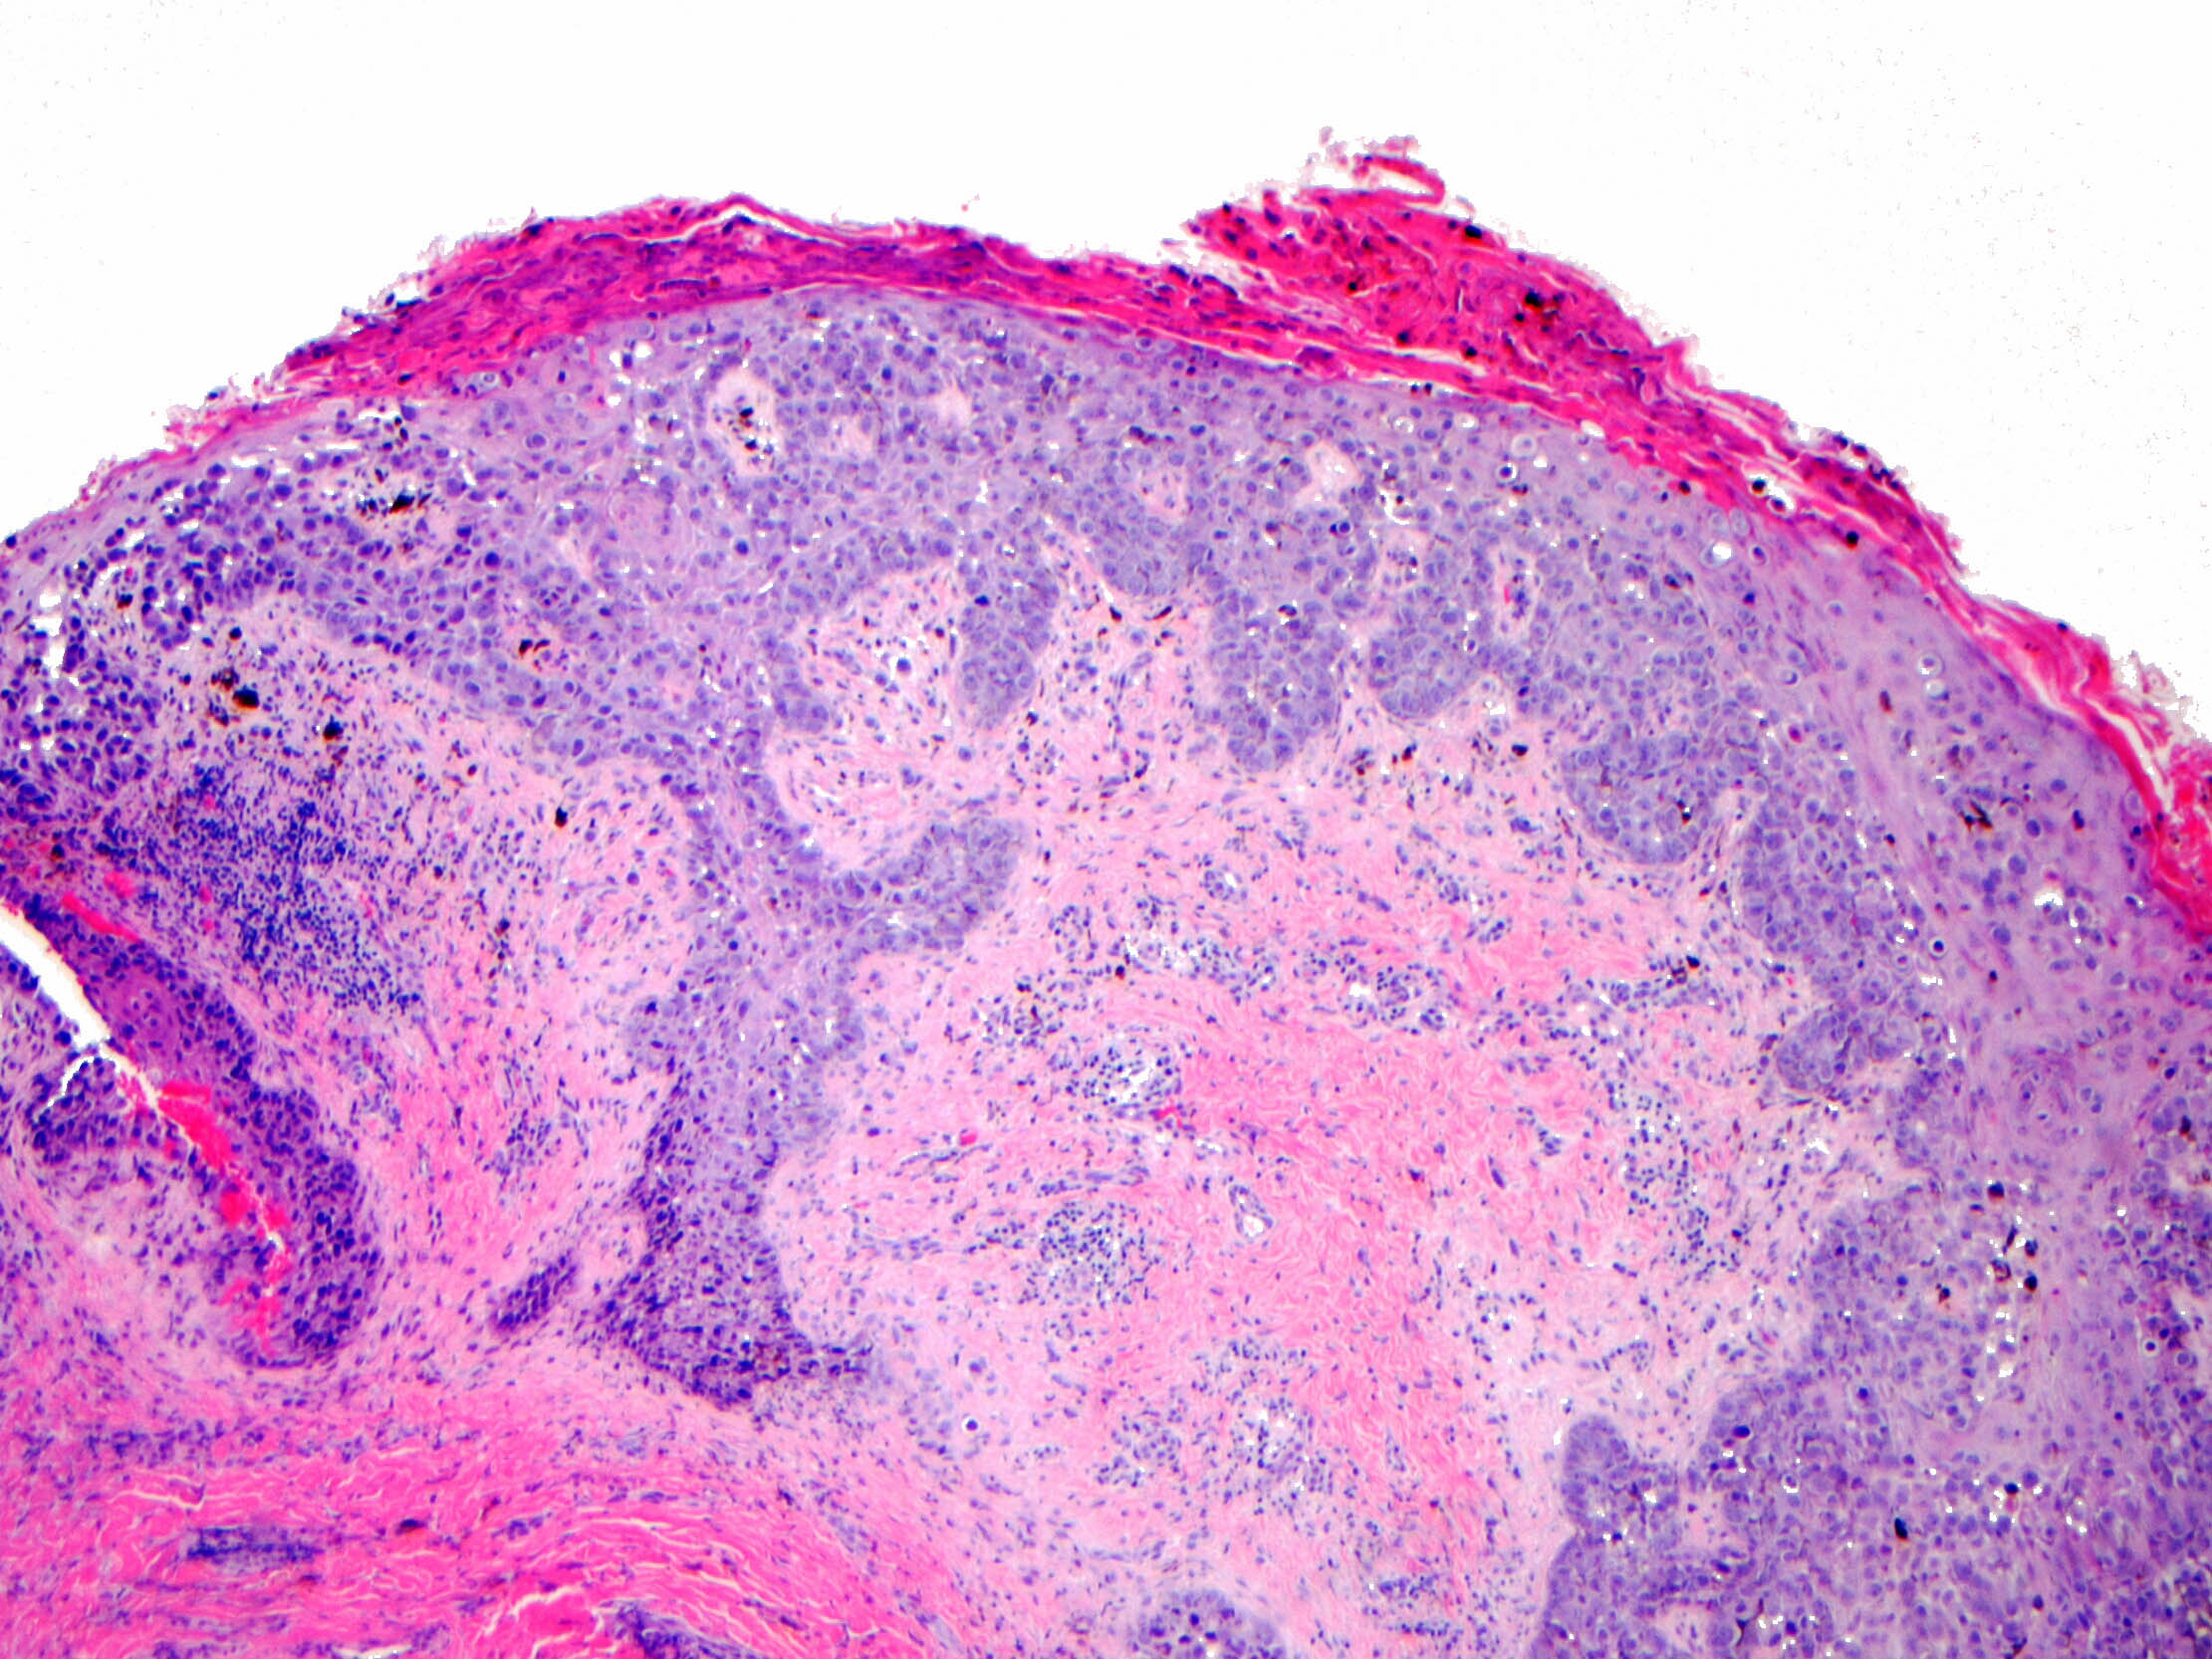

- Single cells or clusters of cells spread throughout the epidermis

- Cells have abundant pale cytoplasm, large irregular nuclei with prominent nucleoli

- Epidermis with hyperkeratosis and possibly ulceration

- Underlying carcinoma is most commonly high grade invasive carcinoma of no special type (NST; 53 - 64%) or DCIS (24 - 43%) (Histopathology 2020;77:181)

Microscopic (histologic) images

Contributed by Anna Biernacka, M.D., Ph.D. and Mary Ann Gimenez Sanders, M.D, Ph.D.